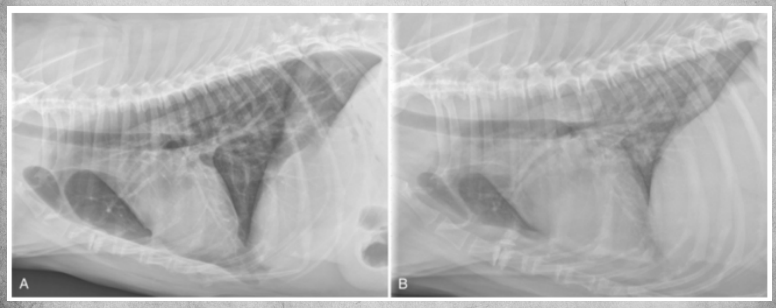

Inspiration vs expiration phases and their affect on thorax xrays.

Same animal in both pics.

● Expiration

– Cardiac silhouette appears larger

– Cranial and caudal margin less

defined